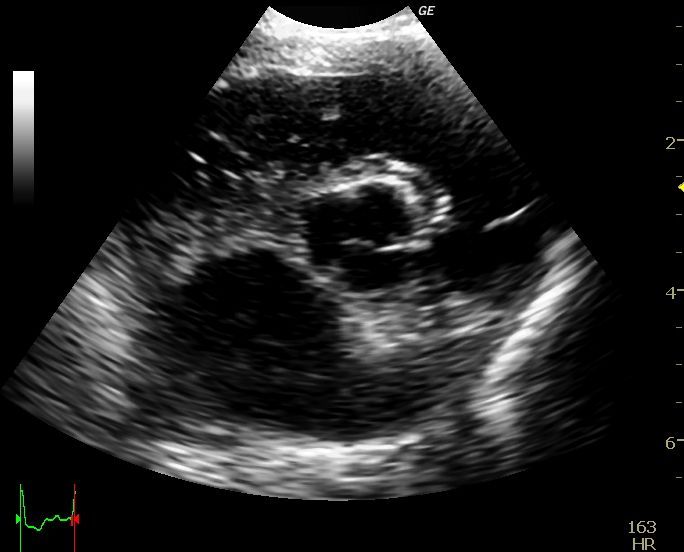

La ecocardiografía es una herramienta imprescindible en el diagnóstico y seguimiento de las patologías cardíacas, tanto congénitas como adquiridas, ya que nos permite visualizar el interior de corazón, pudiendo observar sus paredes, sus válvulas y aportando datos objetivos sobre la funcionalidad cardíaca. Además la ecocardiografía Doppler, (Doppler espectral, pulsado y continuo, y Doppler de flujo color) permite la evaluación de la dirección y la velocidad del flujo sanguíneo a traves del corazón y de los grandes vasos.